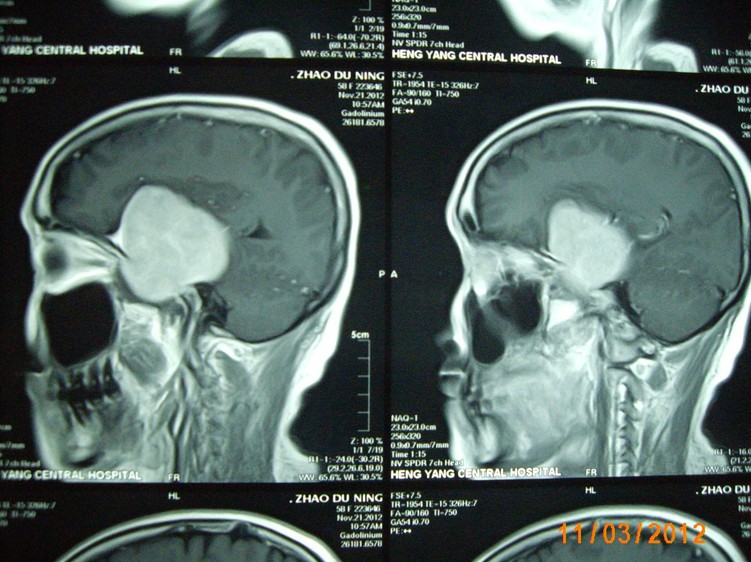

近日,一名來(lái)自常寧的58歲女性患者,因右側(cè)肢體麻木,頭暈3月入住衡陽(yáng)市中心醫(yī)院神經(jīng)外科。頭顱增強(qiáng)磁共振檢查明確右側(cè)中顱窩底巨大腦膜瘤,約10*6*5cm3大小。經(jīng)過(guò)嚴(yán)密的術(shù)前檢查和全科術(shù)前討論,以科室主任鐘三寶主任醫(yī)師為首的手術(shù)組經(jīng)過(guò)4個(gè)小時(shí)的顯微鏡下手術(shù),順利的全切腫瘤。因腫瘤巨大,瘤體切除后局部留下一很大空腔,容易并發(fā)腦組織移位、腦出血,導(dǎo)致嚴(yán)重并發(fā)癥。術(shù)者創(chuàng)新地使用了水囊,逐步減壓等方法,使患者平穩(wěn)地度過(guò)了腦組織復(fù)位關(guān)。術(shù)后未出現(xiàn)任何并發(fā)癥,恢復(fù)良好,順利出院。

(術(shù)前磁共振)